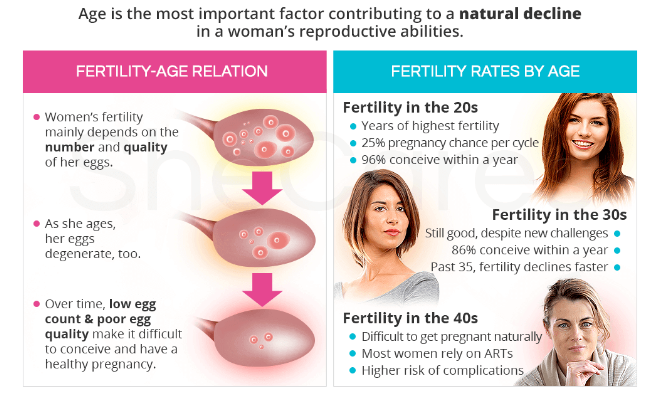

Eggs live in ovaries, and the hormones that control your menstrual cycle cause a few eggs to mature every month.

When your egg is mature, it means it’s ready to be fertilized by a sperm cell.

And, of course, knowing that every year that passes brings you closer to menopause.